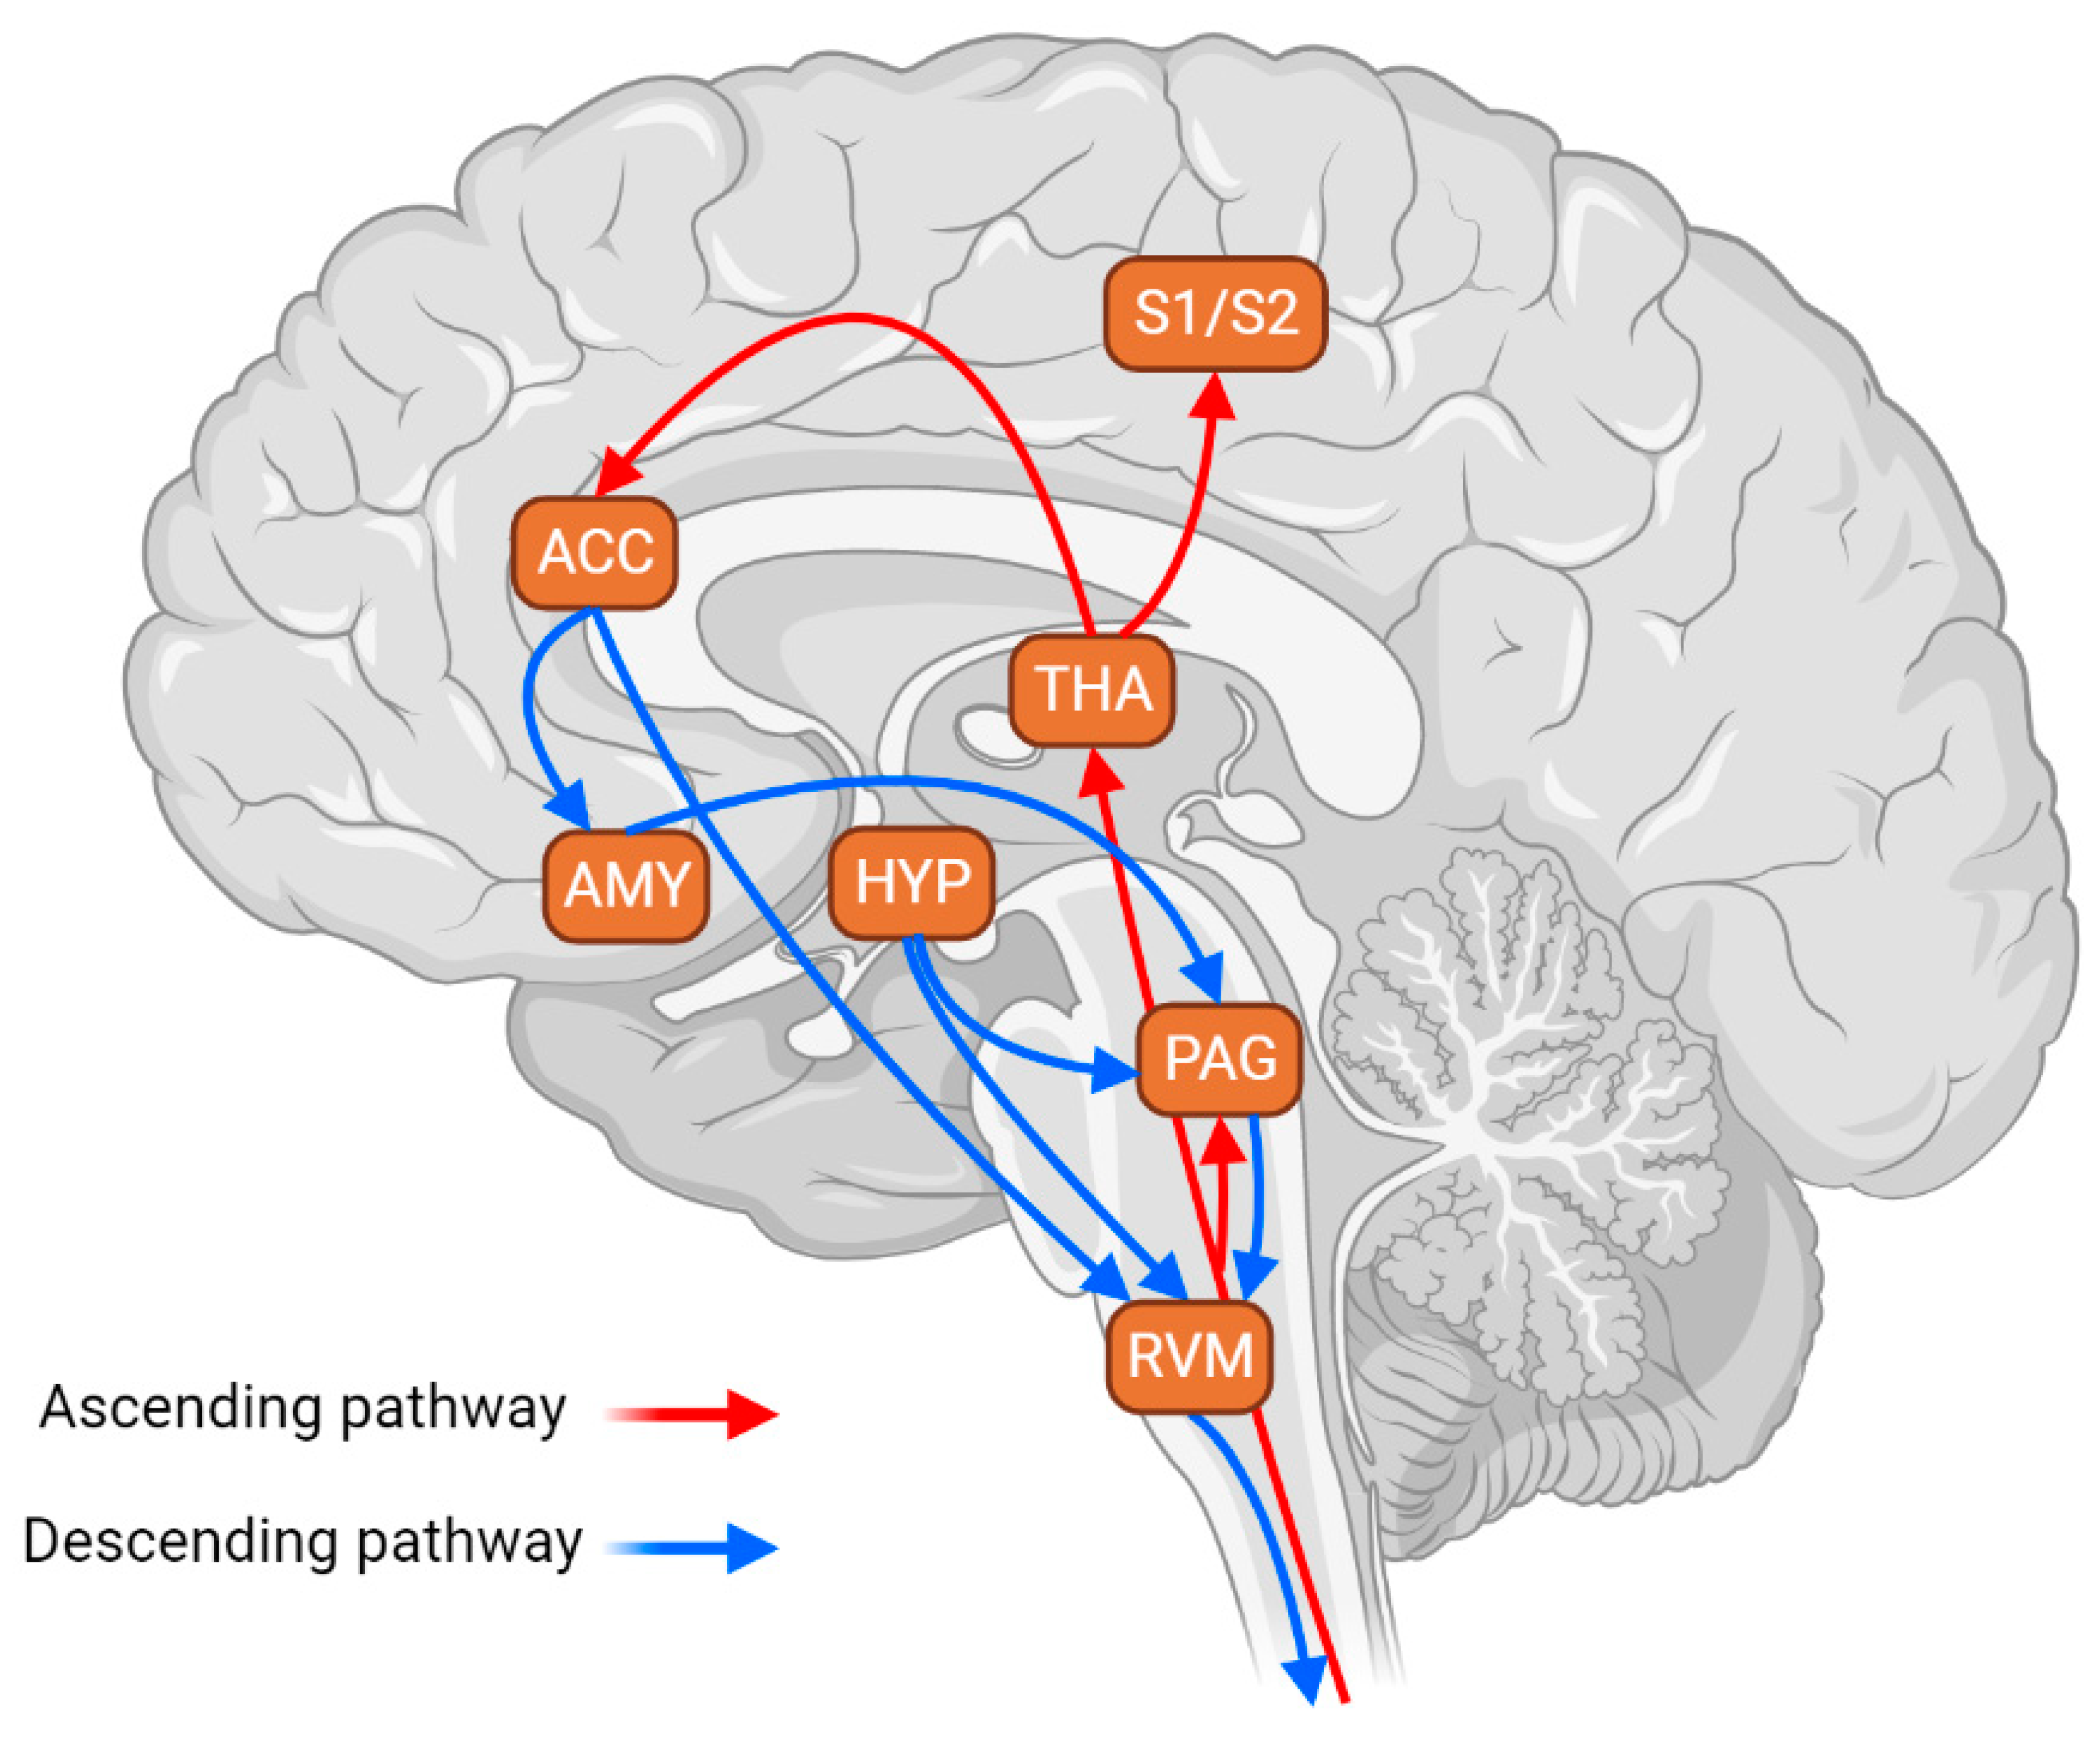

Brain Sciences | Free Full-Text | The Role of The Rostral